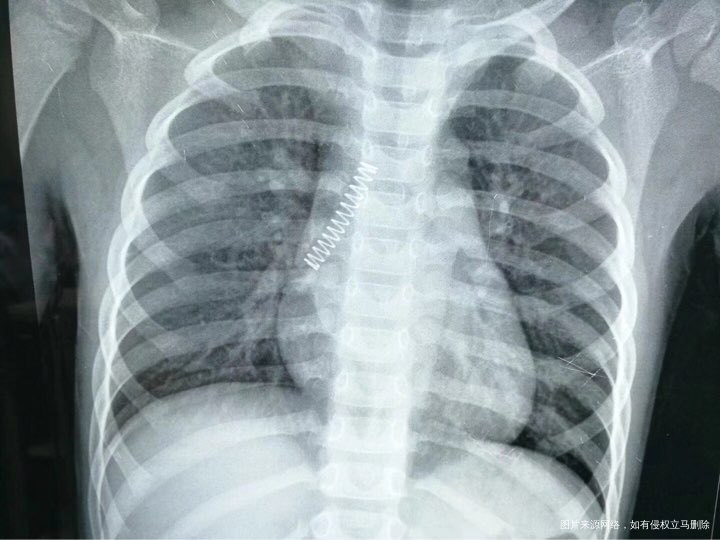

朋友圈一个大夫分享的,他们医院收了个孩子,学电视吞枪自杀,用玩具枪对着嘴里开,结果枪里的弹簧蹦出来,卡到肺里了,做手术才取出来,吓死了